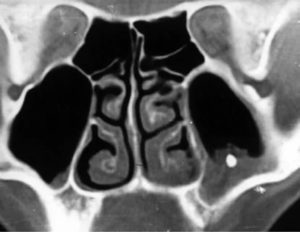

Пневматизация пазух – это не заболевание, а термин. С помощью него врачи характеризуют явления на снимке рентгена или на экране при томографии.

Пневматизация – уровень заполнения пазух воздухом, который при нормальном состоянии двигается без препятствий по носовым проходам.

На снимке можно заметить, что пневматизация:

- сохранена;

- снижена;

- повышена.

В первом случае, нет отклонений от нормы и скорее всего, причина болезни не в постороннем предмете.

Если инородное тело присутствует в гайморовой пазухе, то на это укажет пониженный уровень пневматизации. При этом воздух с трудом циркулирует, что приводит к уменьшению поставок кислорода в организм.